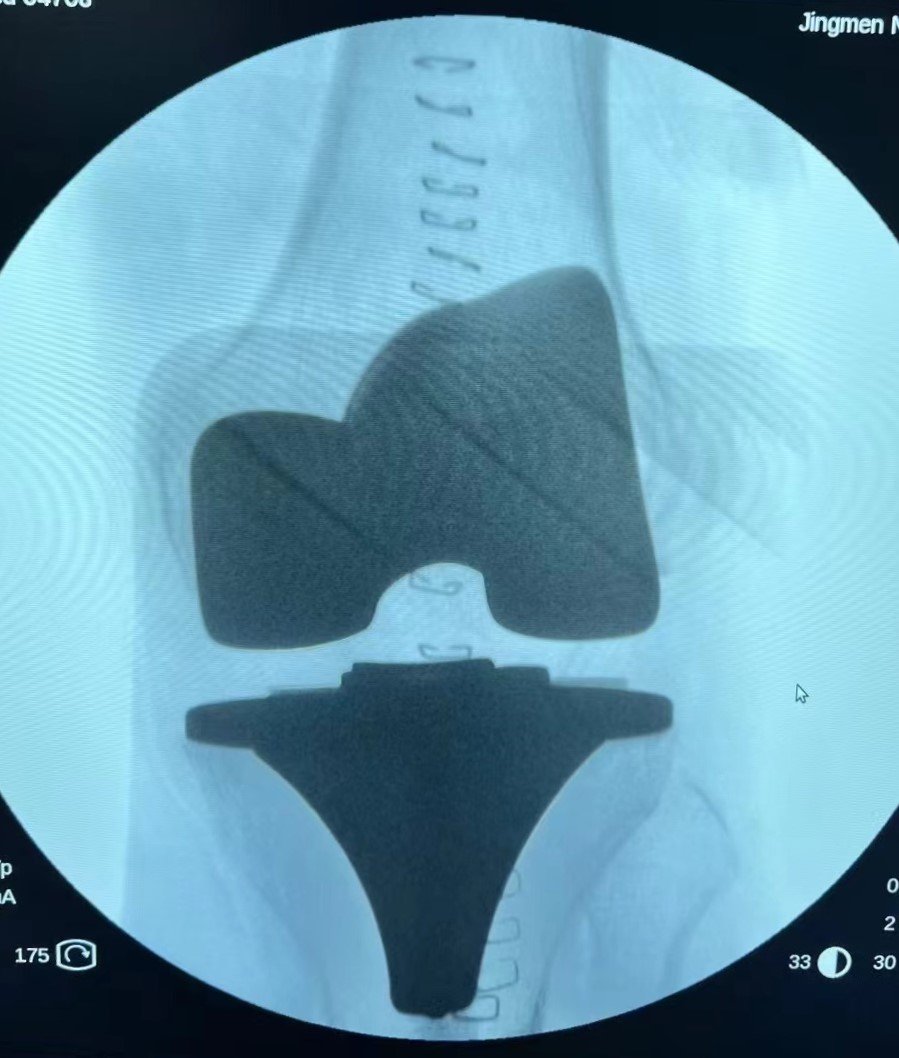

全膝关节置换

膝关节单髁置换术